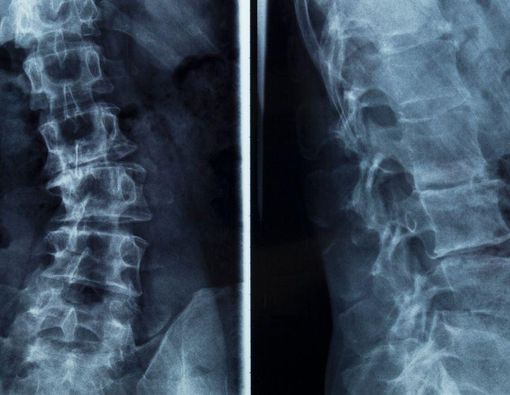

Skoliosis adalah gangguan atau kelainan yang ditandai dengan kelengkungan abnormal pada tulang belakang.

Tulang belakang terdiri dari tumpukan blok bangunan berbentuk persegi panjang yang disebut vertebra. Pada kondisi normal, tulang belakang membentuk kurva dari bahu ke bawah serta terlihat lurus dari belakang.

Tulang hanya akan terlihat sedikit melengkung apabila dilihat dari arah samping. Nah, pada penderita skoliosis, tulang akan terlihat melengkung ke samping meskipun dilihat dari belakang.

Lengkungan ini biasanya membentuk huruf “C” atau “S”.

Diagnosis skoliosis dapat dilakukan lewat pemeriksaan fisik, yang meliputi area bahu, tulang belakang, tulang rusuk, dan pinggul. Tujuannya adalah untuk melihat adanya lengkungan abnormal atau tonjolan pada bagian tersebut.

Selain pemeriksaan fisik, dokter juga dapat melakukan pemeriksaan penunjang. Pemeriksaan untuk mendiagnosis skoliosis antara lain:

- Sinar X dan rontgen

Penggunaan prosedur radiasi diperlukan untuk mendapatkan gambaran citra tulang belakang.